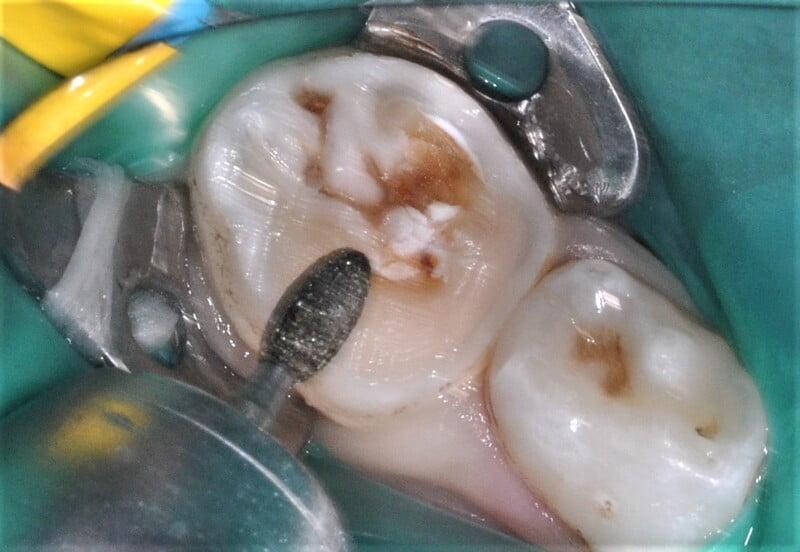

Foi também sugerida a realização de sedação consciente devido à história prévia de falta de colaboração do paciente, tendo sido também aceite pelos responsáveis o recurso a esta técnica de controlo de comportamento, o que possibilitou a execução do plano de tratamento estipulado (fig. 4).

Após a anestesia e a colocação do isolamento absoluto com dique de borracha (fig. 5) foi iniciado o preparo dentário para a colocação de uma coroa de zircónia pré-formada, seguindo as instruções do fabricante. Inicialmente, foi realizada uma redução da superfície oclusal de 1-2 mm, seguindo o contorno oclusal, com uma broca em chama de vela diamantada (fig. 6). De seguida, foi efetuada uma redução supragengival de todas as paredes dentárias com uma inclinação ligeiramente convergente para oclusal. Foram eliminados os contactos interproximais e toda a coroa clínica foi reduzida em cerca de 20-30%, seguido de um cuidadoso desgaste com uma broca em fio de faca diamantada da margem da preparação, cerca de 1-2 mm infragengival, para eliminar todas as margens ou degraus. Todas as linhas de ângulo foram ligeiramente arredondadas (fig. 7).